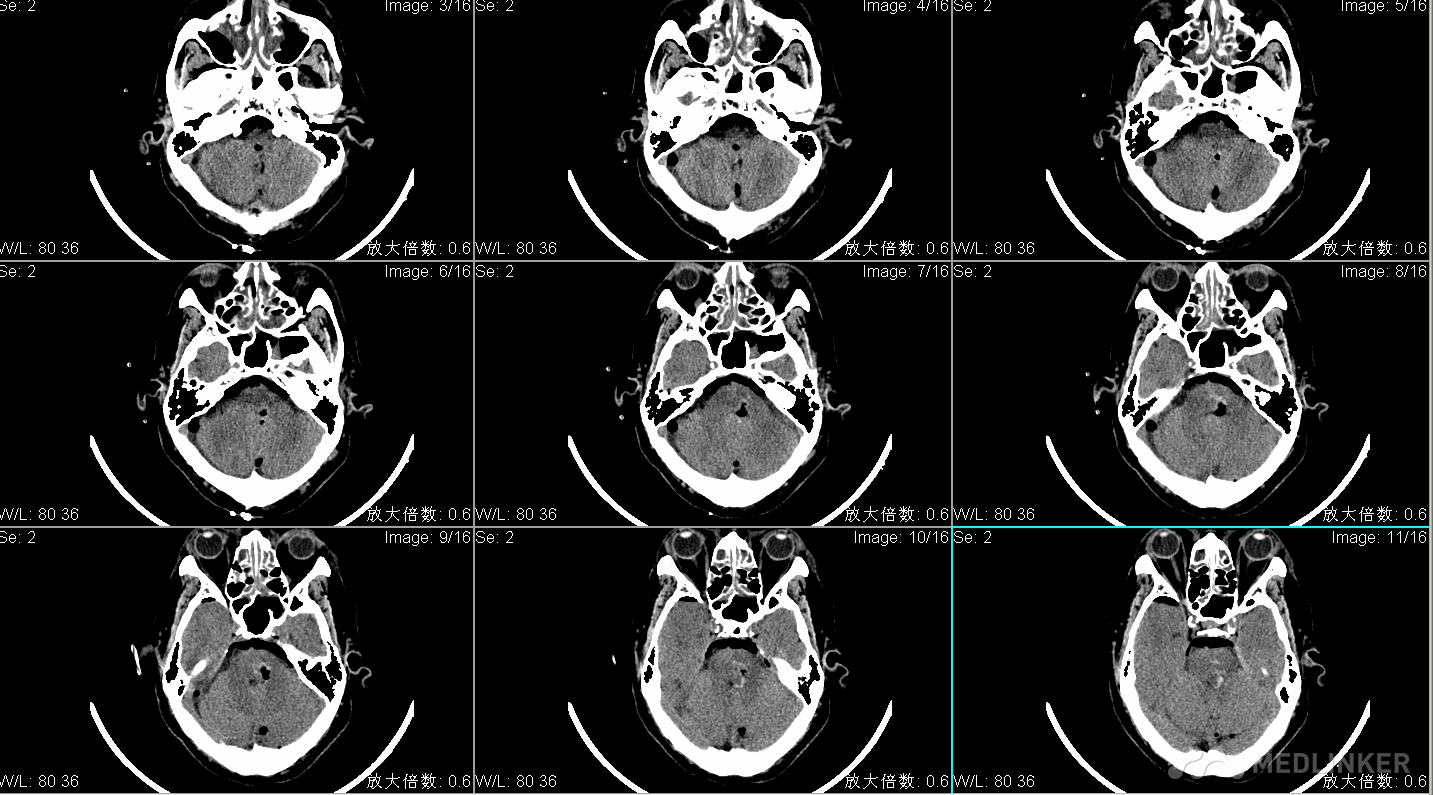

昏迷状态,刺痛不睁眼,无发声,四肢刺痛屈曲 ,GCS5分,双侧瞳孔直径左:右=1:1mm,光反射消失,眼球居中位,额纹对称,颈软,四肢刺痛屈曲,肌张力不高,腱反射(++),生理反射存在,双巴氏征(+)。 头CT显示脑干出血破入第四脑室,出血量约10ml。

术前头CT